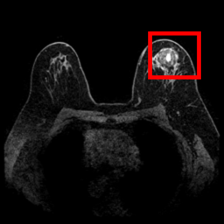

DUKE Breast Cancer Dataset – This dataset, obtained from 922 patients with invasive breast cancers collected at Duke Hospital over 14 years, is one of the largest publicly available breast cancer 3D MRI image datasets, where the task is identifying the presence of breast tumors [23].

Using the trained models with state-of-the-art performance, we follow the protocol detailed in Section 2.4 and present experimental results on interpretability in Figure 3, Figure 4, and Table 3. In particular, Figure 3 illustrates several qualitative examples, while Table 3 displays pointing game accuracy and mean IoU scores. Finally, Figure 4 represents IoU distributions represented in the form of boxplots. Based on these results, we make the observations below.

Qualitative results can be misleading. In Figure 3, we present qualitative interpretability outputs for all methods considered. As can be seen, depending on the selected subset of images and the method, both accurate and inaccurate interpretability maps can be found. These findings emphasize the danger of making strong claims about interpretability methods based solely on qualitative results, including attention maps.